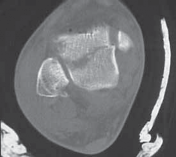

Displaced, intra-articular posterior talar body fractures present largely in the coronal plane ( TECH FIG 4).

4.

I prefer to position the patient prone, on a sterile bump, and access the fracture through the posteromedial approach.

5.

Before inflation of a tourniquet, I recommend inserting medial, distal-third tibial and calcaneal external fixation half-pins. This will allow for application of a small femoral distractor, which aids in ankle and subtalar joint distraction.

6.

A headlamp worn by the operating surgeon aids visualization in this approach.

38.

Narrow Hohmann retractors are gently applied medially and laterally within the ankle joint, retracting the posterior tibial nerve and artery and FHL tendon, respectively. This allows exposure of the posterior talar fragment.

1.

The fracture is reduced using dental probes.

2.

Smooth Kirschner wires are inserted, posterior to anterior, provisionally fixing the fracture.

39.

The fracture is fixed either by interfragmentary, parallel screw fixation or a well-contoured mini-plate and interfragmentary screws.

The posterior mini-plate is contoured in a curvilinear fashion to securely buttress the posterior talus.